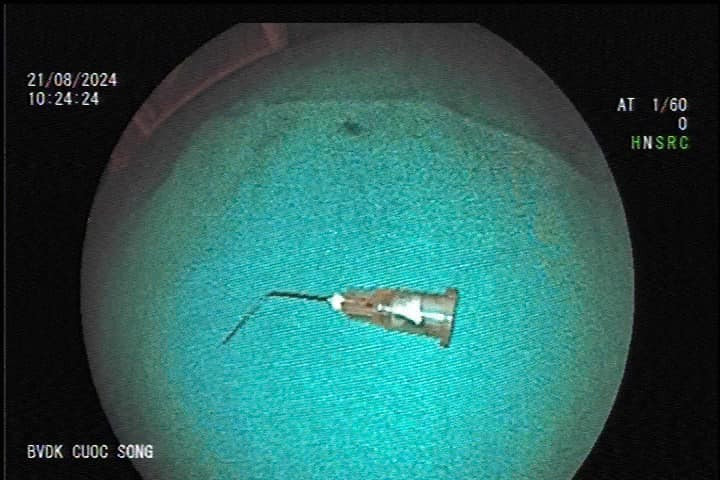

Các bác sĩ tiến hành gây mê nội soi phát hiện mũi kim nằm trong lòng dạ dày. Dị vật là kim tiêm loại bơm 5ml bẻ cong. Rất may, dị vật chưa đâm thủng thành dạ dày.

| Mũi kim được gắp ra từ dạ dày của bệnh nhân. Ảnh BVCC |